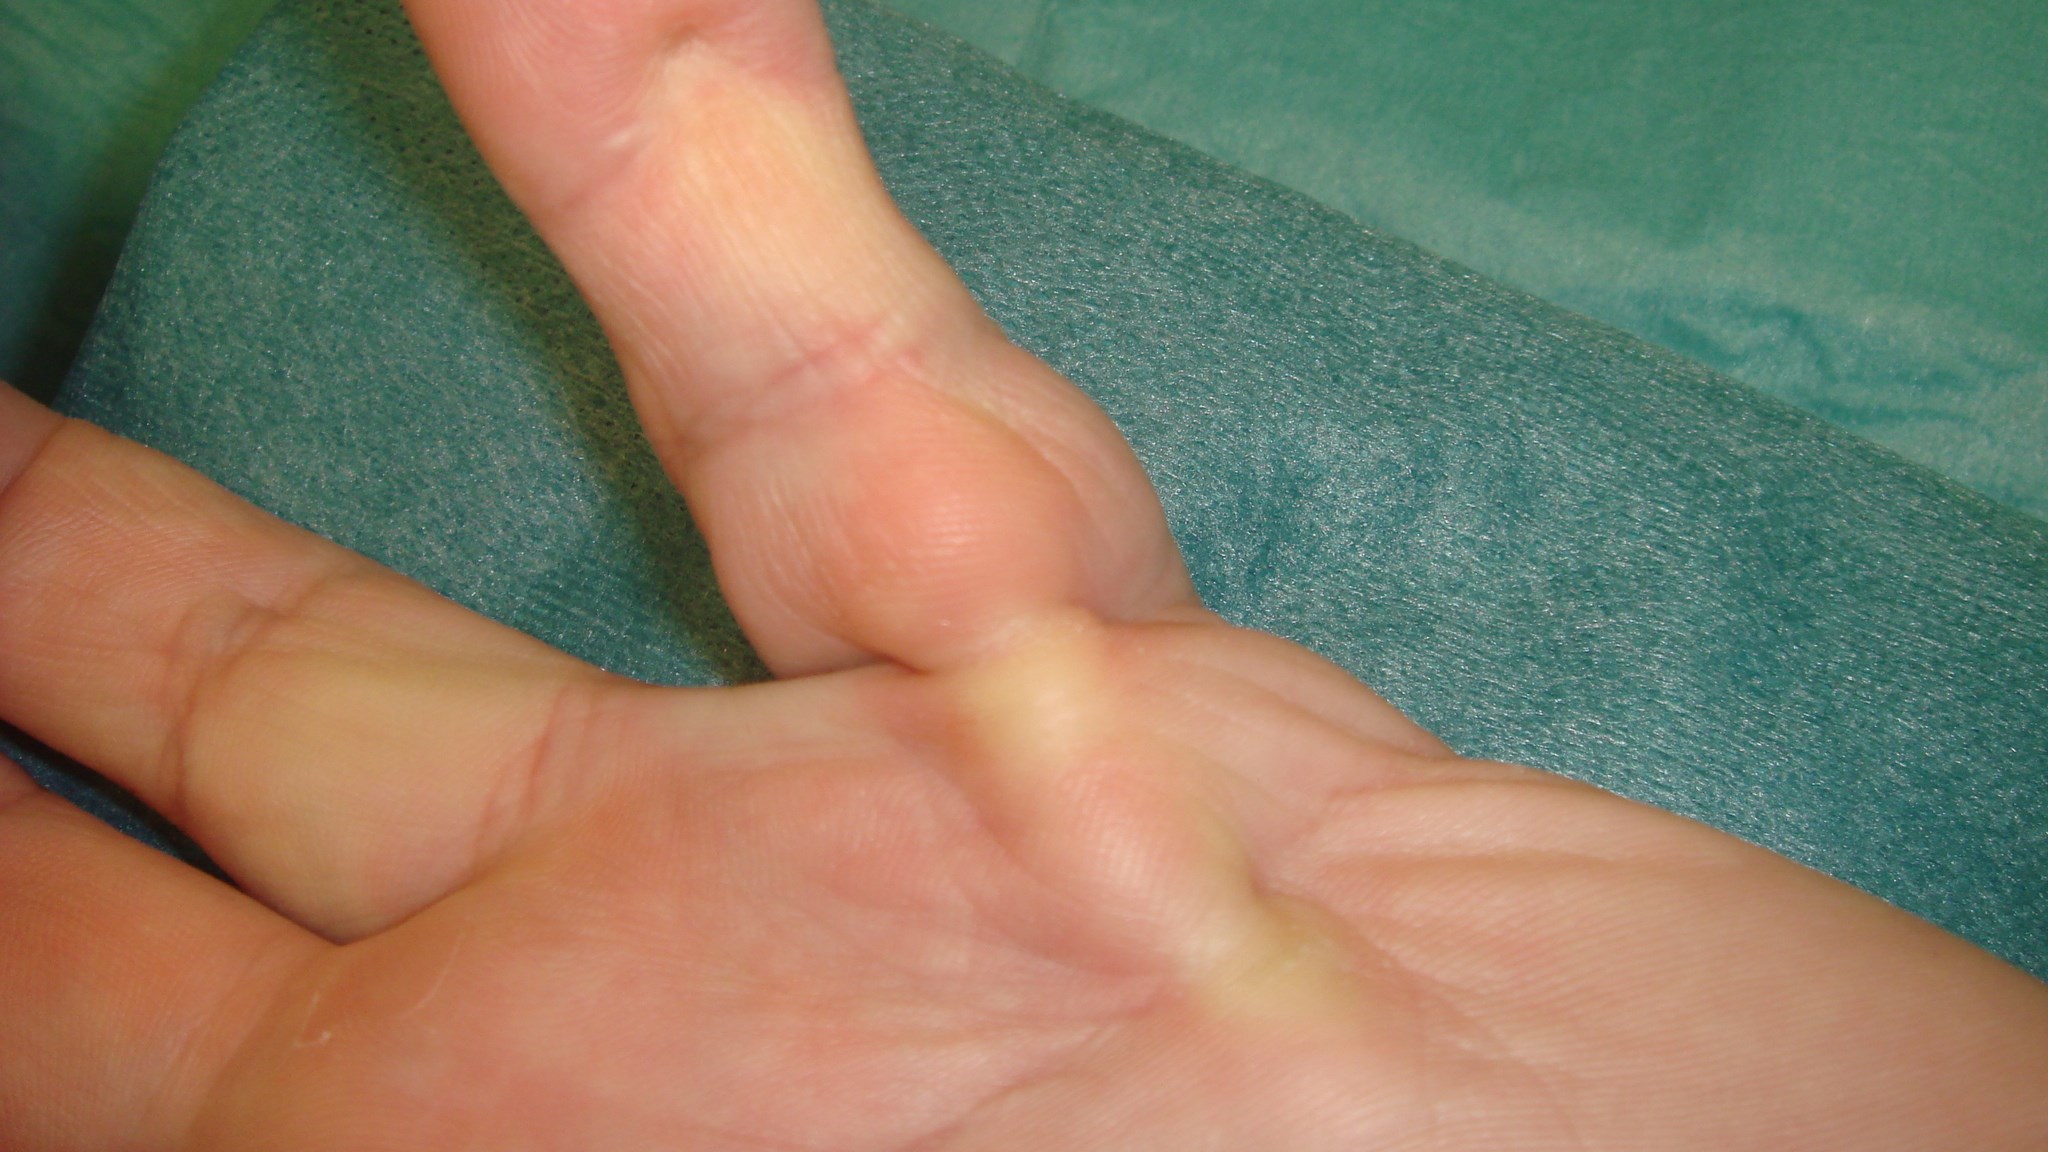

Enchondrom